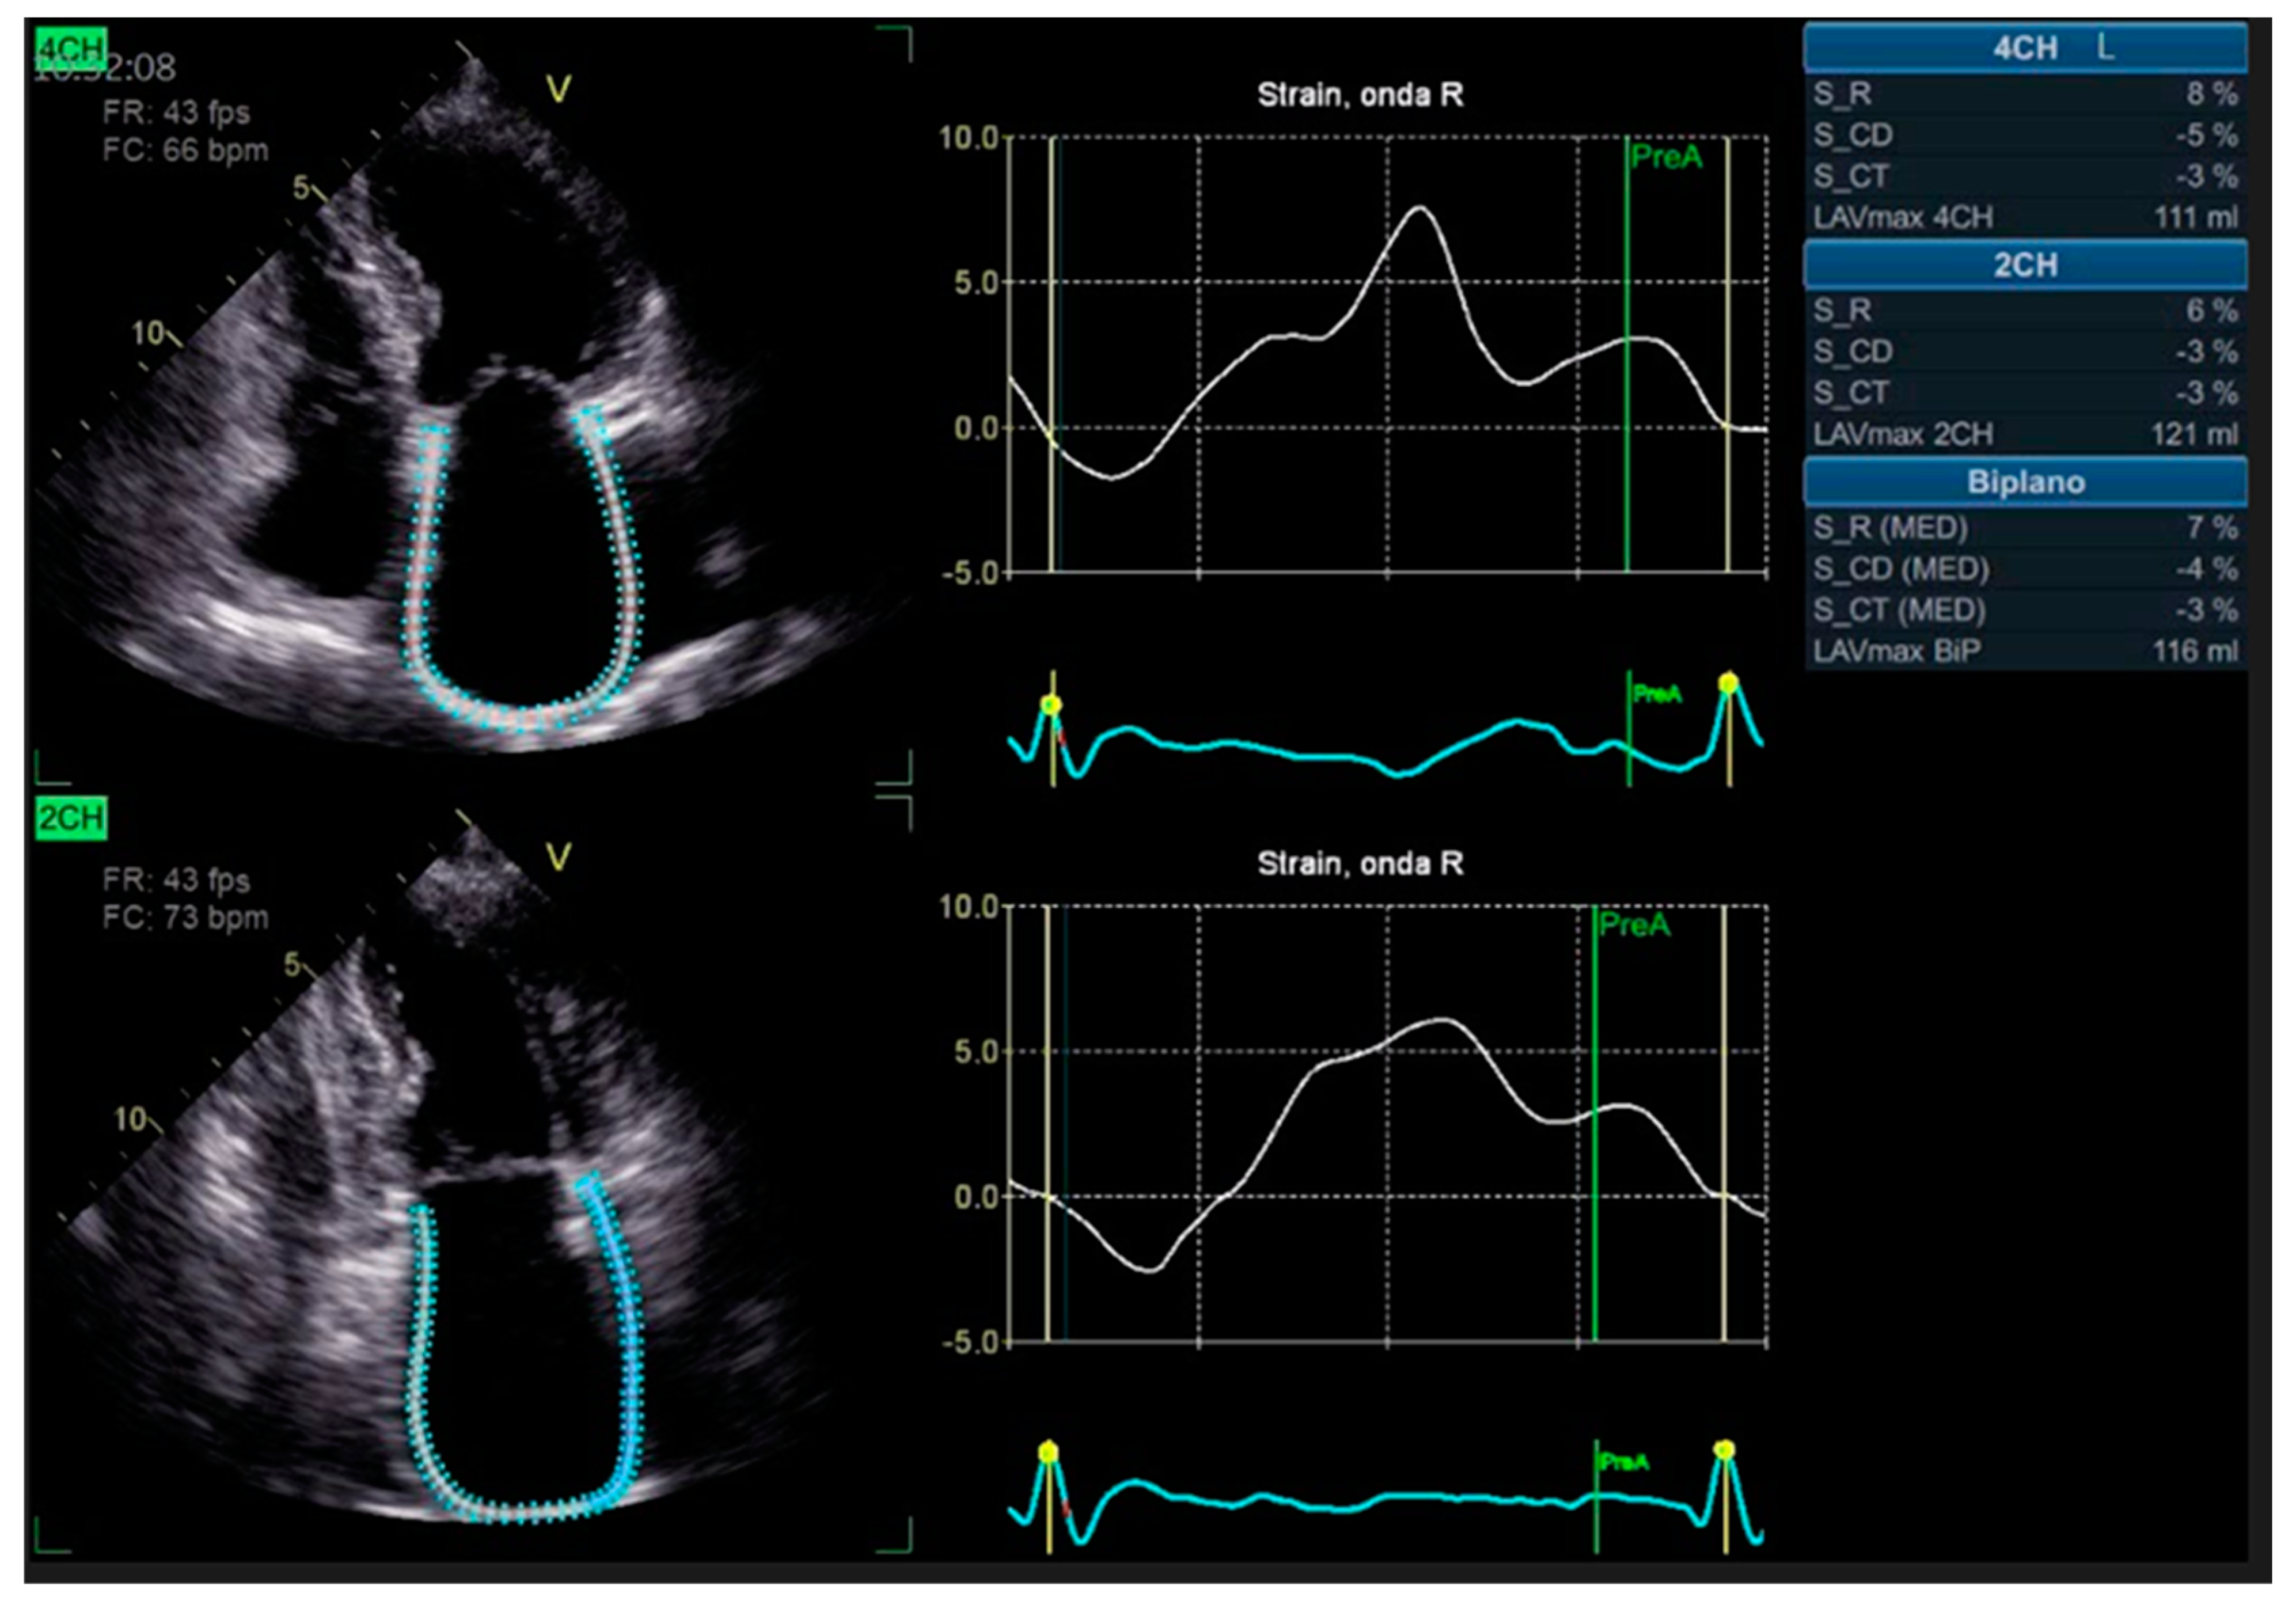

- Zhu, S.; Xie, Y.; Qiao, W.; Tian, F.; Sun, W.; Wang, Y.; Wu, C.; Li, H.; Yi, L.; Zhong, Y.; et al. Impaired left atrial function in clinically well heart transplant patients. Int. J. Cardiovasc. Imaging 2021, 37, 1937–1945. [Google Scholar] [CrossRef]